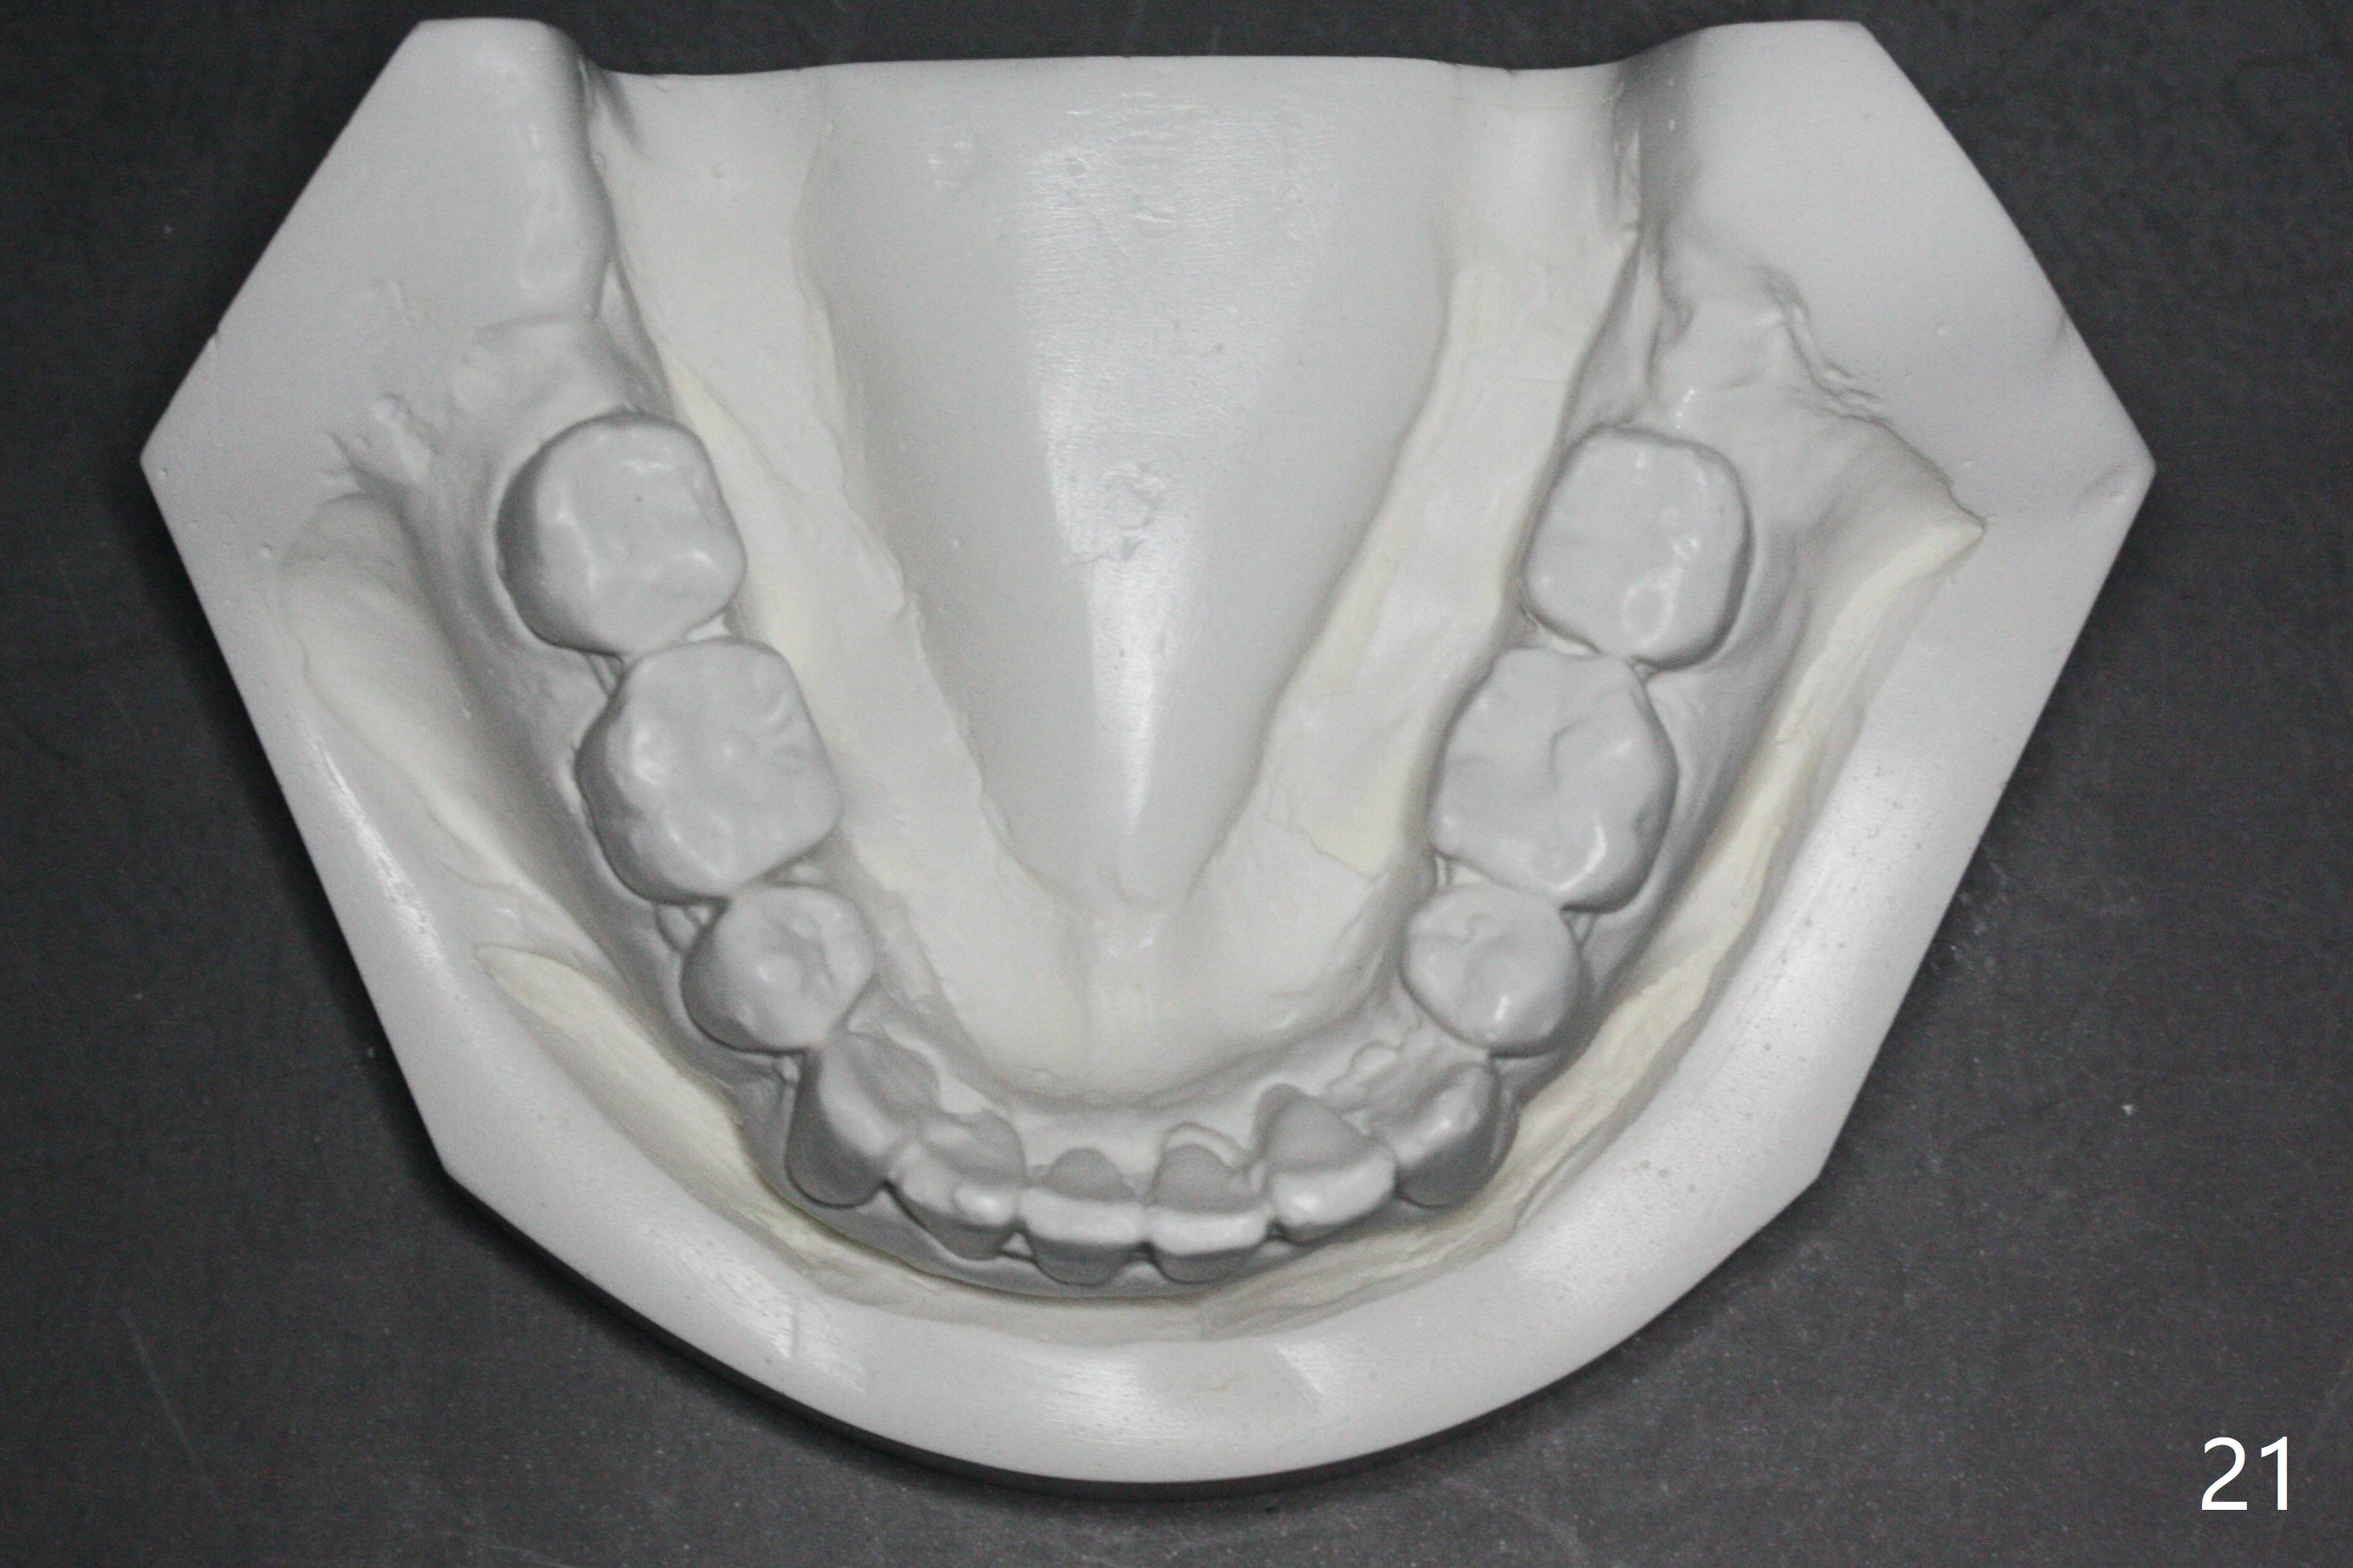

Enough Space For Crowding After Extraction? A 47-year-old man requests orthodontic treatment following SRP in other office (Fig.1-11). For severe crowding and midline shifting, extraction of four of the 1st bicuspids is imminent. Is it enough? To answer the question, model surgery is performed (Fig.12-16). 1st visit: periodontal maintenance, orthodontic consent (emphasizing oral hygiene) extract 4s and possibly L8s and separators. The beauty of this vist is that after local anesthesia and extraction including L8s, it is painless and easy to remove calculus from the proximal surfaces of the neighboring teeth. It is much easier to place separators after extraction. It is expected that there is no gingival erythema when the patient returns for bracketing. Take photos of UR3, similar to Fig.3. Molar banding is also anticipated to be easy with separator placement after extraction. Return to Ortho Cases Xin Wei, DDS, PhD, MS 1st edition 11/23/2017, last revision 04/28/2019